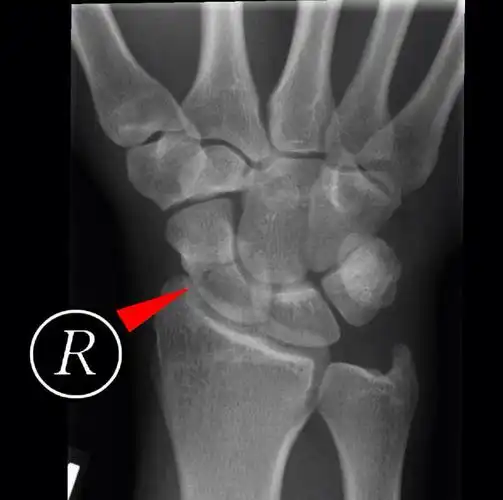

郑州市骨科医院会诊病例 腕舟骨骨折

右手腕舟状骨骨折